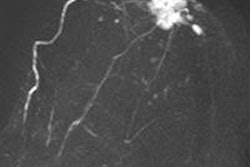

Stehouwer and team included 123 patients from the MR Mammography of Nonpalpable Breast Tumors (MONET) trial in their study. Between January 2006 and May 2009, patients with mammographically detected BI-RADS 3-5 microcalcifications underwent 3-tesla breast MRI (Achieva, Philips Healthcare) before breast biopsy. Two breast radiologists reviewed all MRI exams of the histopathologically confirmed index lesions.

At pathology, 40 of 123 (33%) lesions proved malignant, and 70% of those were DCIS, the rest were invasive carcinoma. The two observers detected all invasive malignancies at MRI, as well as 79% (observer 1) and 86% (observer 2) of in situ lesions. MRI in addition to conventional imaging led to a significant increase in area under the receiver operating characteristic (ROC) curve from 0.67 to 0.79 for observer 1 and to 0.80 for observer 2.

However, only low- and intermediate-grade DCIS are affected in this instance and not high-grade DCIS or invasive carcinomas -- in fact, almost all the DCIS lesions detected on MRI were high-grade in the study.